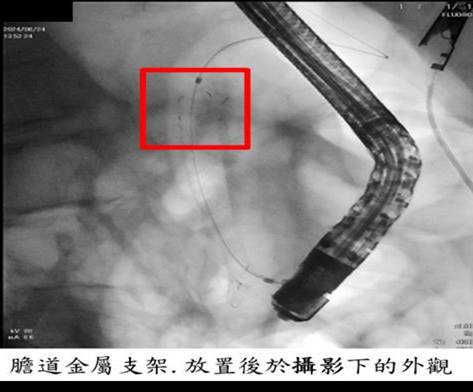

因此在112年最初,採用「內引流」方式,透過內視鏡檢查,在膽道中放置了塑膠支架,以引流膽汁,改善黃疸症狀。然而,由於塑膠支架孔徑較小,約2~3個月後就容易產生阻塞或膽管炎,因此阿嬤需要反覆更換膽道塑膠支架。

所幸6月起金屬支架納入健保給付,經過與家屬的討論並告知這項新消息,考量阿嬤的高齡和手術風險,決定改採用膽道金屬支架,其孔徑較大,不容易阻塞,並且能夠維持較長的通暢時間(約6個月)。金屬支架能有效控制惡性腫瘤引起的膽道阻塞,並緩解阿嬤出現的黃疸、皮膚癢、腹痛、發燒和食慾不振等相關併發症。

透過膽道金屬支架引流,阿嬤的黃疸指數得以恢復,增加了她的舒適度。在生命的最後階段,她能清醒地與家人共度時光,這是一件幸福的事情。